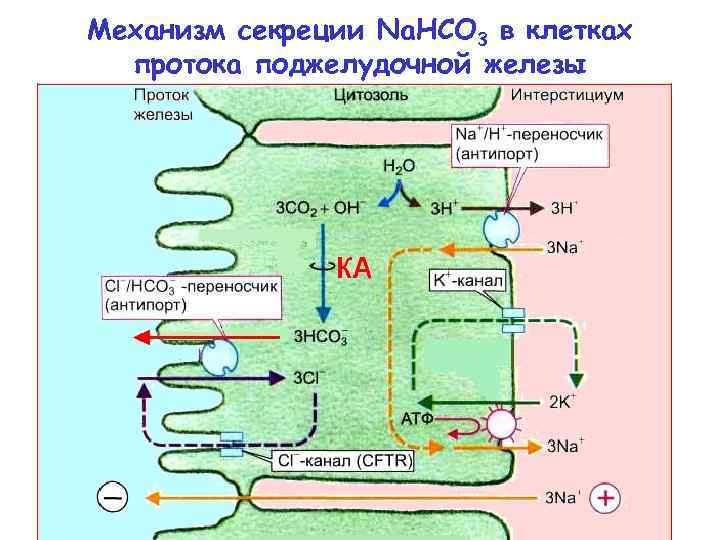

Механизм секреции Na. HCO 3 в клетках протока поджелудочной железы

Механизм секреции Na. HCO 3 в клетках протока поджелудочной железы

Механизм секреции Na. HCO 3 в клетках протока поджелудочной железы • НСОз- попадает в проток железы с помощью анионного обмена c Cl- (пассивный антипорт) • Параллельно подключённый Cl--канал обеспечивает рециркуляцию Cl--канал (CFTR — Cystic Fibrosis Transmembrane Conductance Regulator) • Необходим Na+/H+ антипорт через базолатеральную мембрану • Транспорт НСОз- зависит от Na+/К+-АТФазы на базолатеральной мембране • Жидкость в протоке заряжается отрицательно по отношению к интерстициальной (выход Cl- в просвет протока и проникновение К+ в клетку через базолатеральную мембрану), что способствует пассивной диффузии ионов Na+ в проток железы по межклеточным плотным контактам.

Механизм секреции Na. HCO 3 в клетках протока поджелудочной железы • НСОз- попадает в проток железы с помощью анионного обмена c Cl- (пассивный антипорт) • Параллельно подключённый Cl--канал обеспечивает рециркуляцию Cl--канал (CFTR — Cystic Fibrosis Transmembrane Conductance Regulator) • Необходим Na+/H+ антипорт через базолатеральную мембрану • Транспорт НСОз- зависит от Na+/К+-АТФазы на базолатеральной мембране • Жидкость в протоке заряжается отрицательно по отношению к интерстициальной (выход Cl- в просвет протока и проникновение К+ в клетку через базолатеральную мембрану), что способствует пассивной диффузии ионов Na+ в проток железы по межклеточным плотным контактам.

Механизм секреции Na. HCO 3 в клетках протока поджелудочной железы Дефект Cl—канала, обеспечивающего рециркуляцию Cl--канал (CFTR — Cystic Fibrosis Transmembrane Conductance Regulator) у больных муковисцидозом (Cystic Fibrosis), делает секрет поджелудочной железы тягучим и бедным анионами НСОз.

Механизм секреции Na. HCO 3 в клетках протока поджелудочной железы Дефект Cl—канала, обеспечивающего рециркуляцию Cl--канал (CFTR — Cystic Fibrosis Transmembrane Conductance Regulator) у больных муковисцидозом (Cystic Fibrosis), делает секрет поджелудочной железы тягучим и бедным анионами НСОз.

Механизм секреции Na. HCO 3 в клетках протока поджелудочной железы • Высокий уровень секреции НСО 3 - возможен, по всей видимости, потому что • НСО 3 - вторично активно транспортируется в клетку с помощью белка-переносчика, осуществляющего сопряженный транспорт Na+/ НСО 3 - (симпорт, белок-переносчик NBC, на первом рисунке не изображен) • Возможен выход НСО 3 - через люминальную мембрану через канал (второй механизм)

Механизм секреции Na. HCO 3 в клетках протока поджелудочной железы • Высокий уровень секреции НСО 3 - возможен, по всей видимости, потому что • НСО 3 - вторично активно транспортируется в клетку с помощью белка-переносчика, осуществляющего сопряженный транспорт Na+/ НСО 3 - (симпорт, белок-переносчик NBC, на первом рисунке не изображен) • Возможен выход НСО 3 - через люминальную мембрану через канал (второй механизм)